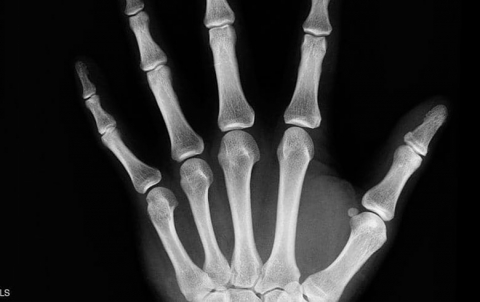

هشاشة العظام

يتم الاحتفال باليوم العالمي لهشاشة العظام في 20 أكتوبر من كل عام. يدعو هذا اليوم لنشر الوعي حول أسباب هذه...

يقول العلم إنه كلما تقدم الإنسان في العمر، أصبحت عظامه أكثر رقة وأقل كثافة، الأمر الذي يجعلها عرضة لأمراض عدة،...